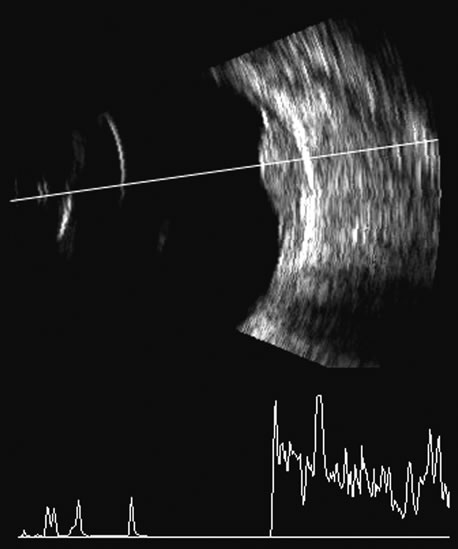

in Medicine. New York, Plenum Press. 1978 14. Coleman DJ, Jack RL: B-scan ultrasonography in diagnosis and management of retinal detachments. Arch Ophthalmol 90:29, 1973 15. Bronson NR, Fisher YL, Pickering NC: Ophthalmic Contact B-Scan Ultrasonography for the Clinician. Westport, CT, International Publication, 1976 16. Downey DB, Nicolle DA, Levin MF, Fenster A: Three-dimensional ultrasound imaging of the eye. Eye 10:75, 1996 17. Coleman DJ, Daly SW, Atencio A, et al: Ultrasonic evaluation of the vitreous and retina. Semin Ophthalmol 13:210, 1998. 18. Wu G, Silverman RH, Coleman DJ, et al: In vivo thickness of human detached retina by ultrasonic signal processing. Graefes Arch Clin Exp Ophthalmol 227:21, 1989 19. Coleman DJ, Rondeau MJ: Diagnostic imaging of ocular and orbital trauma. In Shingleton BJ, Hersh PS, Kenyon KR (eds): Eye Trauma, pp 25–40. St. Louis, Mosby-Year Book, 1991 20. Clemens S, Kroll P, Rochels R: Ultrasonic findings after treatment of retinal detachment by intravitreal

survey of cases in Northern Ireland between 1965 and 1980. Trans Ophthalmol Soc UK 105:114, 1986 45. Silverman RH, Coleman DJ, Lizzi FL, et al: In-vivo volume determination by ultrasound. Invest Ophthalmol (Suppl) 32:1194, 1991 46. Coleman DJ, Lizzi FL, Silverman RH, et al: A model for acoustic characterization of intraocular tumors. Invest Ophthalmol Vis Sci 26:545, 1985 47. Coleman DJ, Silverman RH, Rondeau MJ, et al: Correlations of acoustic tissue typing of malignant melanoma and histopathologic